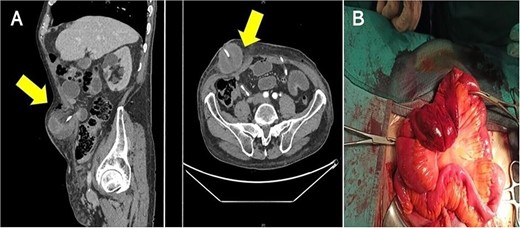

An 82-year-old white male (height: 174 cm, weight: 68 kg, body mass index: 25.3 kg/m2) presented with a history of gross hematuria that had been ongoing for 2 months. Cystoscopy revealed a large mass (3 × 2 cm) on the right wall of the bladder; computed tomography and MRI showed cT2bN1M0 bladder cancer. Medical records revealed that the patient received radical external beam radiation therapy for locally advanced prostate cancer 5 years ago and that he had abdominal surgery as an infant for appendectomy. His bladder tumor was removed with endoscopic technique and he was diagnosed a high-grade (pT2) urothelial carcinoma. He then underwent RARC with ureterocutaneous urinary diversion and pelvic lymph node dissection. On the seventh postoperative day, the patient complained of abdominal pain and nausea. Body temperature was 38.5°C. Physical examination revealed a distended abdomen and a large, irreducible, painful abdominal lump next to the right stoma diversion. Laboratory tests showed leukocytosis (21 000/ml) and increased C-reactive protein (19.58 mg/dl). Abdominal computed tomography showed that a part of the small intestine was protruding between the right ureter and the transverse fascia and was strangulated, causing an obstruction in the intestine (Fig. 1A). Emergency laparotomy revealed prolapse and strangulation of the small intestine through the space between the right ureter and the transversalis fascia, resulting in discoloration of the small intestine and ureter of interest (Fig. 1B). The strangulation was released, but there was no improvement in blood flow in sections of the small bowel strangulated, so intestinal resection and reconstruction was performed. The ischemic tract of the ureter was resected and a new right uretero-cutaneous anastomosis with use of ureteral stent single J (Ch 6) was created. The clinical course of the patient, who was discharged from the hospital 28 days after the surgery, remained stable during follow-up.

(A) Computed tomography shows the small intestinal herniation from the space between right ureter and trasversalis fascia; the arrows show hernial orifice; (B) surgeons observed engorgement of the bowel loops.